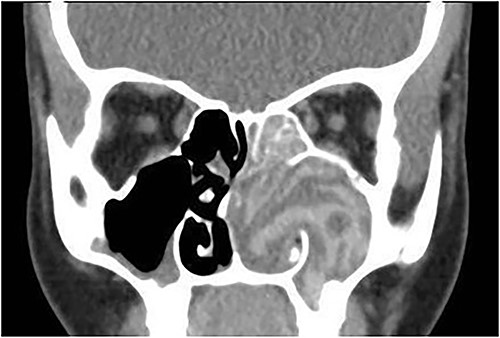

A 13-year-old male presented with progressive right-sided nasal obstruction followed by slowly progressive right eye proptosis noticed by parents for 1 year duration. CT scan of the paranasal sinuses (Fig. 2) confirmed the diagnosis of AFS. The child underwent FESS and received medical treatments post-operatively. The patient remained symptom-free for 4 years follow-up.

Axial CT paranasal sinuses shows the right ethmoid and sphenoid sinuses with complete obliteration and hyperdense (metallic) contents. It is associated with expansion of the ethmoid sinuses and lateral displacement of the right lamina papyracea causing right eye proptosis.